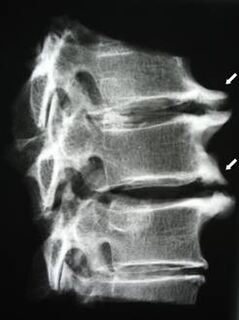

In the initial stages, osteochondrosis is detected by MRI.Later, the pathology can be diagnosed using radiography.X-rays of the cervical spine show a decrease in the distance between the vertebrae, pathological changes in the facet joints and osteophytosis.